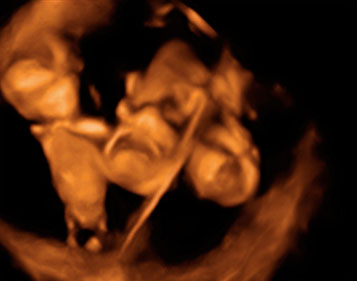

Ecografía Embarazo 4D Semana 12 - CRIBADO DEL PRIMER TRIMESTRE